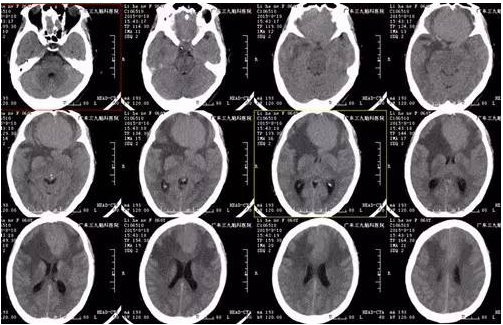

↑术前CT

李阿姨,62岁,断断续续头痛6年,当地医院治疗能有所缓解,近半年间断出现少语发作,为求进一步治疗来我院就诊,入住神经外一科,MR提示前颅窝底占位性病变,呈均匀强化,基底位于前颅窝底,病变大小约5.9*5.3cm*4.9cm,术前CTA,肿瘤血运丰富,大脑前动脉受挤压后移,考虑嗅沟脑膜瘤。